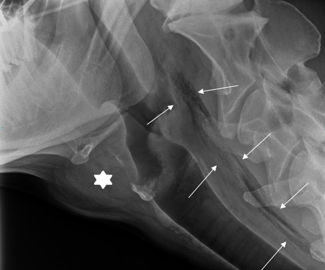

Après plusieurs examens (radiographie, échographies et endoscopies), le diagnostic tombe : Marguerite a un abcès pharyngé qui s’étend le long de l’encolure sur 15 cm et dont le point d’inoculation se situe à l’entrée de l’œsophage. L’origine la plus probable du traumatisme est bien l’administration du premier bolus, aggravé par la seconde. En effet, c’est l’unique cause rapportée, avec l’administration d’aimant, des traumatismes du pharynx. Le pronostic est alors réservé car il dépend de la rapidité du diagnostic. Un traitement chirurgical n’est pas recommandé ici au vu de la situation de l’abcès (position dorsale) et de la large diffusion de l’infection dans l’encolure. Un risque de pneumonie, par fausse déglutition et passage dans les poumons, est aussi présent.